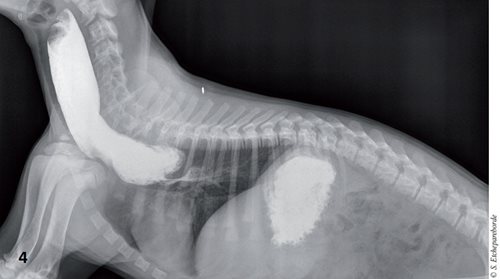

Sur ces mêmes radiographies, on recherchera des signes de pneumonie par aspiration. Un œsophagogramme permet de confirmer la présence d’une obstruction œsophagienne et d’un jabot (Figure 4).

œsophagogramme du dalmatien : on note une accumulation du produit de contraste dans le jabot œsophagien ainsi que le rétrécissement à la base du cœur.